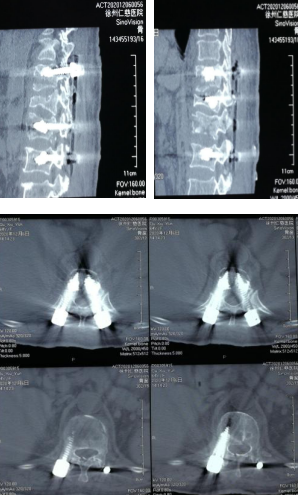

待骨水泥凝固,上连接棒,撑开,+减压手术

术后CT影像